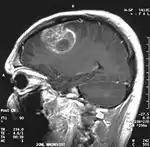

Мультиформна гліобластома (англ. Glioblastoma multiforme, GBM) — найбільш розповсюдженна і найбільш агресивна форма пухлини мозку, яка становить до 52 % первинних пухлин мозку і до 20 % всіх внутрішньочерепних пухлин. Незважаючи на те, що гліобластома є найбільш розповсюдженою первинною пухлиною мозку, на 100 тисяч жителів Європи і Північної Америки реєструється всього 2-3 випадки захворювання[3]. Термін «гліобластома» передбачає два варіанти цієї хвороби: гігантоклітинна гліобластома і гліосаркома.